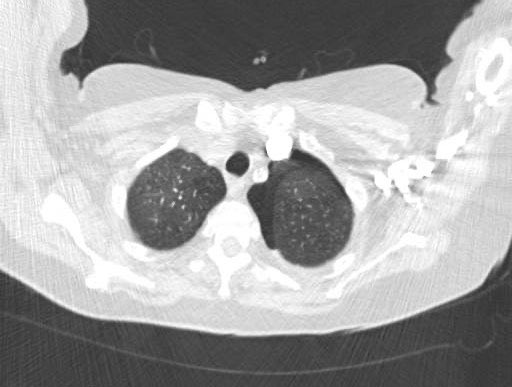

5/10 A CT thorax was performed which confirmed our suspicion. A left sided pneumothorax was identified. See CT images below: